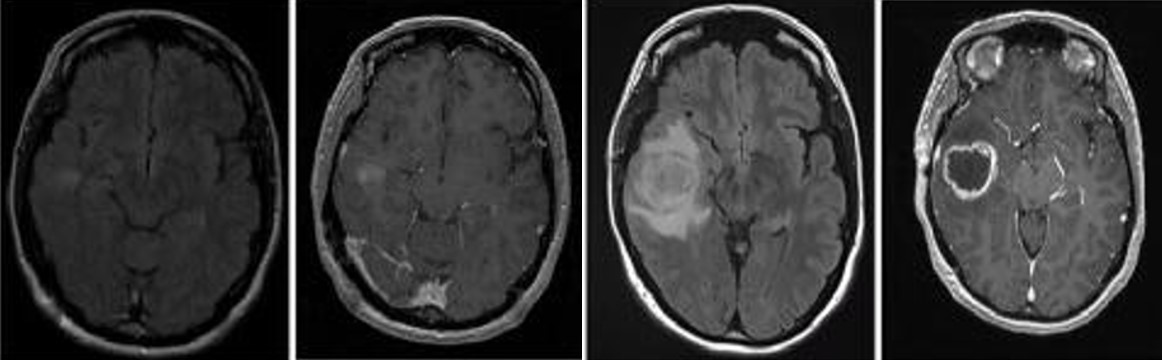

胶质母细胞瘤(Glioblastoma , GBM)是中枢神经系统中比较常见的神经上皮肿瘤,是恶性程度最高的原发性脑肿瘤也是最致命的实体瘤,被世界卫生组织归类为Ⅳ级胶质瘤。GBM 预后差,被诊断后的平均中位生存期为 14个月,其5年生存率为 5%。尽管目前在外科手术,放化疗等医学治疗手段取得了不错的进展,但在延长患者的生存期上仍未取得突破。因此,目前迫切需要筛选鉴定出有效的GBM生物标记物,探索GBM的治疗靶标并解析GBM的发病机理,为GBM的早期诊断及预后评估提供新策略以延缓患者的生存期。

崔红娟教授团队就GBM标志物的筛查、鉴定以及如何管控EGFR在GBM的表达开展了深入研究。首先, GBM患者组织的免疫组化病理检测以及生物信息学分析发现一种能够参与异染色质形成的H3组蛋白甲基化阅读器CBX3(Chromobox 3)在GBM患者中异常高表达,并且与GBM的预后和恶性分级密切相关。功能检测表明了CBX3 在体外和体内显著促进 GBM 细胞的增殖、侵袭和肿瘤发生。从机制上来说,我们通过Ch-IP和Co-IP等一系列生物技术实验证明了CBX3促进GBM 的恶性进展是EGFR 依赖性的,并且进一步揭示了GBM患者发病机理的一条全新的信号通路CBX3-PARK2/STUB1-EGFR。该研究不仅丰富了GBM表观遗传学的研究,也为该信号通路作为GBM潜在治疗靶点的可行性提供了坚实的依据。伊莉影片